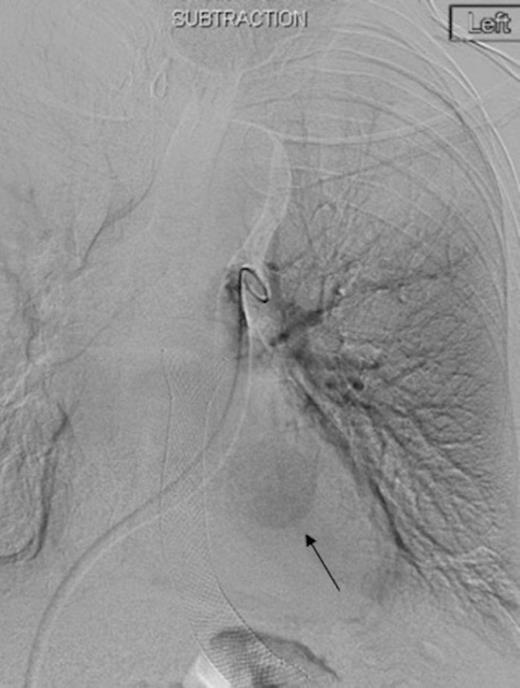

Digital subtraction angiography post deployment of the AVP 4 device in the PA branch feeding the aneurysm (arrow). No residual or collateral filling seen

Coronal reconstruction of CTPA taken 2 days after embolisation demonstrating successful ongoing exclusion of the PA aneurysm. Note the AVP (arrow) and continued filling of unaffected lower lobe segmental pulmonary arterial branches